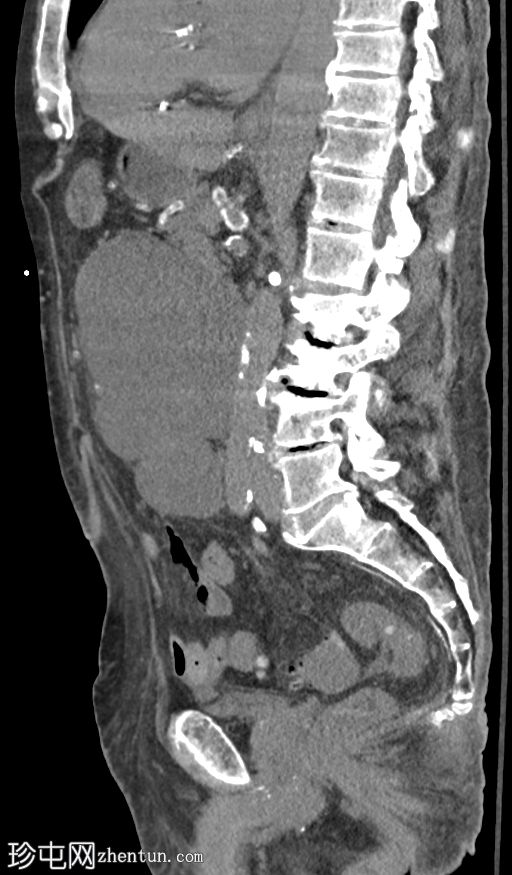

CT

轴位

1.jpeg

平扫

冠状动脉和主动脉瓣膜钙化明显。广泛的腹部动脉粥样硬化。胆结石。双肾萎缩。左髂窝移植肾形态大致正常。

右髂窝移植肾边界不清,呈低密度,周围环绕着一个大的分叶状复杂囊性肿块。